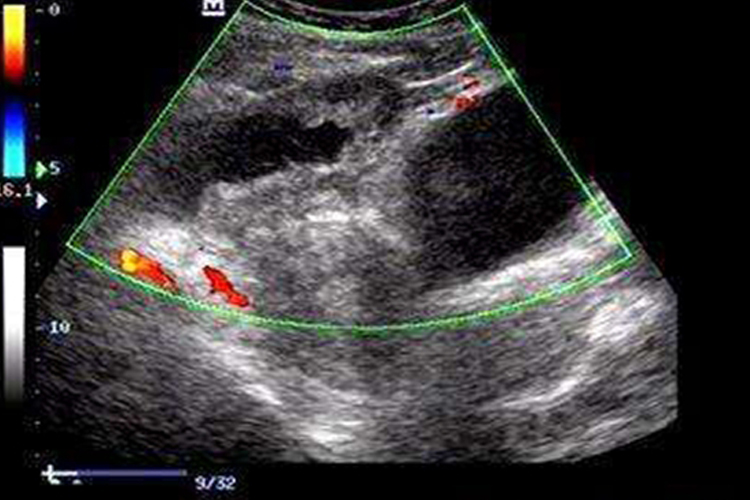

卵巢囊肿蒂扭转表现为盆腔囊性包块,超声可探及扭转蒂部。蒂部扭转主要表现为条索状的低回声,当瘤蒂较长时扭转的蒂和囊肿会生成典型的囊性、实性“双肿块”声像。